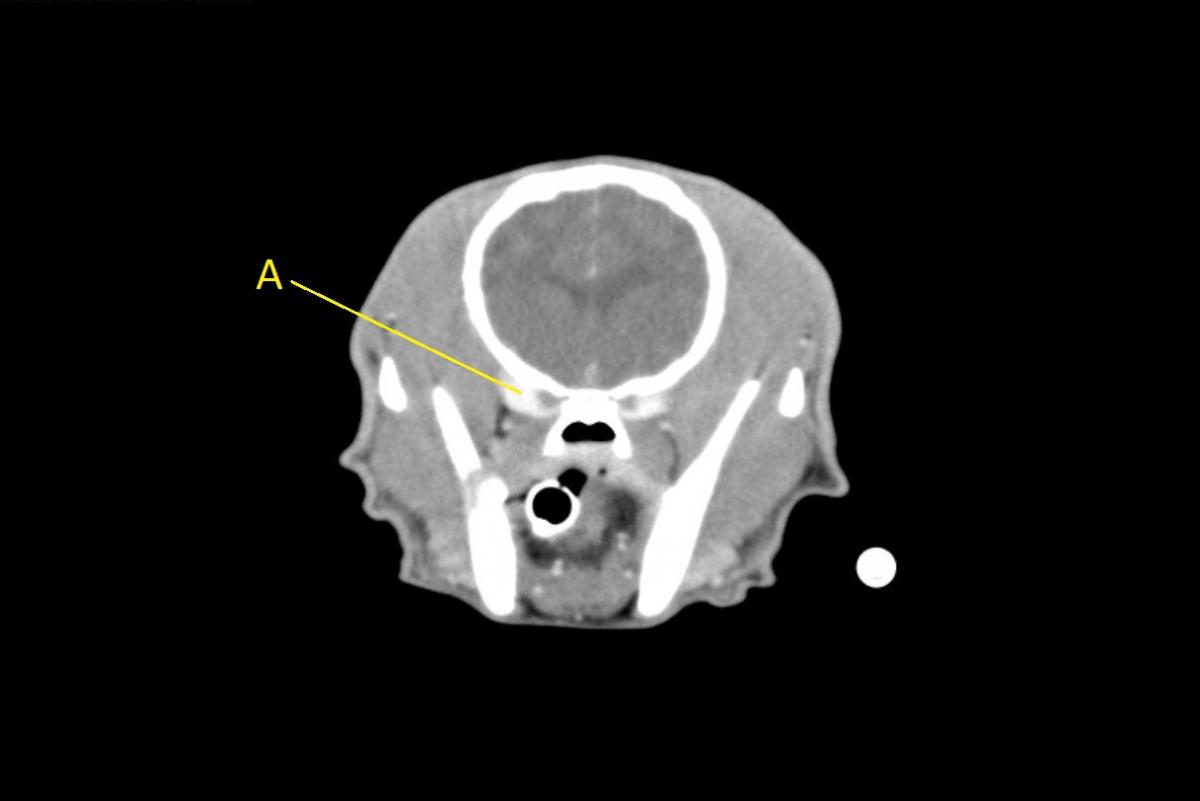

Q. Identify the structures labeled below:

A. ophthalmic venous plexus